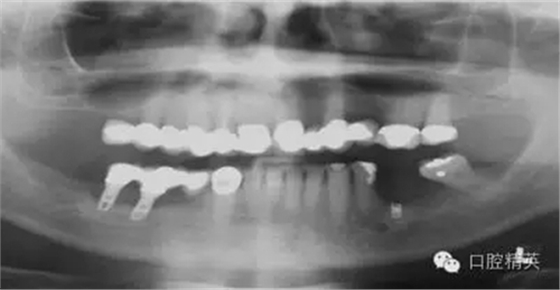

圖2a:術(shù)后曲面斷層片顯示兩顆種植體分別異位于左右側(cè)上頜竇中

另一個(gè)和醫(yī)生僅用兩維放射線檢查造成的特殊并發(fā)癥是種植體進(jìn)入上頜竇。(圖2a-c)可能成為上頜竇異物的有牙齒,牙根,印模材料,牙科器械,近年來(lái)又增加了一個(gè)—種植體??上攵?,從上頜竇中取出異物對(duì)患者來(lái)講是創(chuàng)傷很大的。